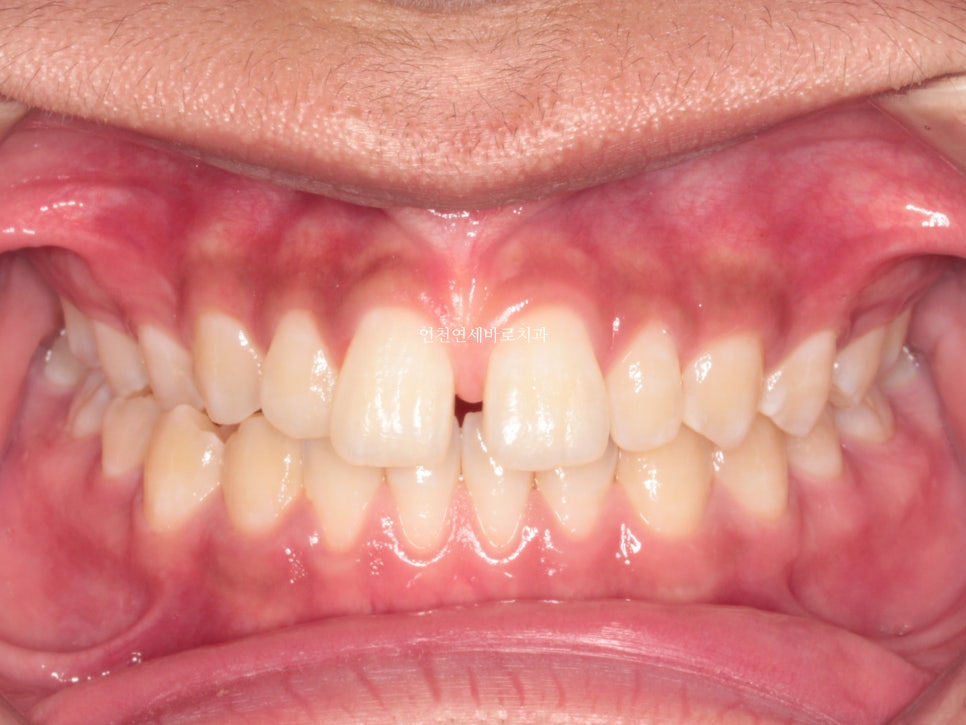

치료 받으러 온 고1 남학생입니다.

앞니가 벌어진 것도 문제였지만

화살표쪽에 보이는 반대교합도 문제였습니다.

인비절라인으로 치료를 하기로 했습니다.